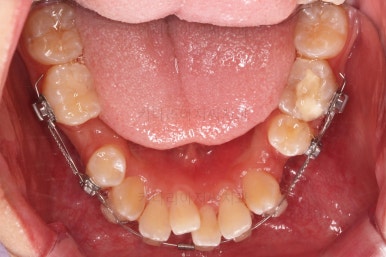

초진 시 입안의 모습입니다.

앞니가 많이 삐뚤고, 송곳니가 부각되어 덧니처럼 보이네요.

장치를 처음 부착한 모습입니다.

이번 환자분이 선택하신 장치는 데이몬 클리어라고 하는 자가결찰 세라믹 장치인데요.

순차적으로 장치를 붙여가며 치아를 가지런하게 합니다.

가지런하게 하는 단계를 거친 뒤,당기기 과정에 들어가는데요.